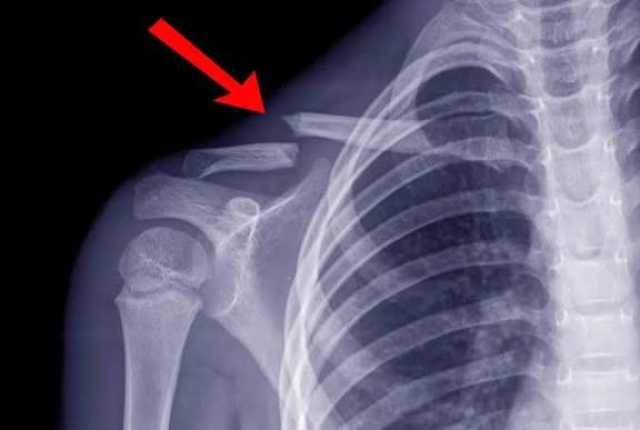

ما الذي يحدث عند كسر الترقوة؟كيف يتم تشخيص كسر الترقوة؟

يبدأ التشخيص بفحص سريري يتبعه تصوير بالأشعة السينية لتحديد:

ـ مكان الكسر

ـ نوعه

ـ مدى انفصال الأجزاء

وفي الحالات المعقدة يستخدم الأطباء الأشعة المقطعية قبل وضع خطة العلاج.